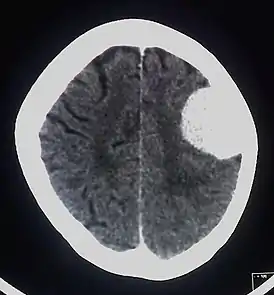

КТ

КТ с контрастированием сопровождается умеренным-выраженным гомогенным усилением в большинстве случаев. При помощи КТ диагностируются около 90% менингиом. Главная роль КТ – демонстрация изменения костей и кальцинатов в опухоли.